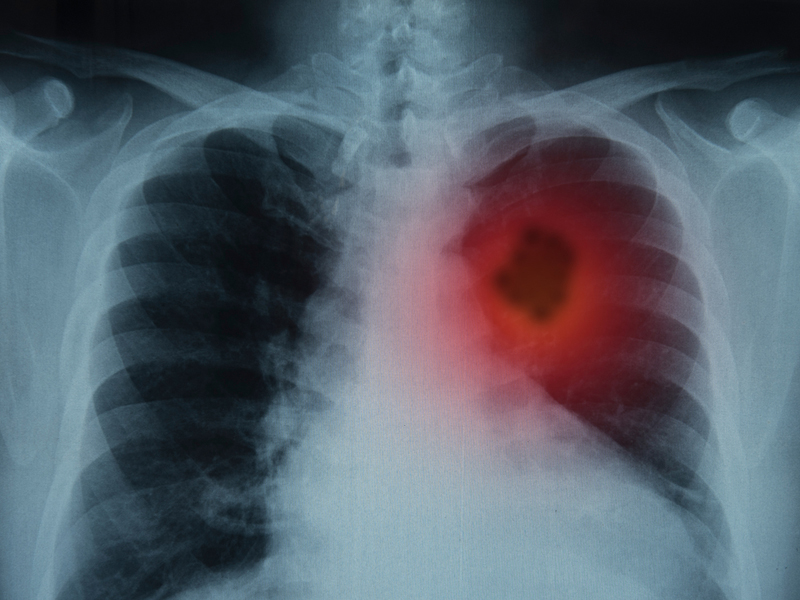

傳言:喝咖啡會增加患心髒病的風險。

真相:並不會。

美國心髒病協會、歐洲心髒病學會等權威機構經過研究認為,適量飲用咖啡,不會增加患心髒病和心血管疾病的風險。

而且研究表明,對於那些已經患上冠心病,甚至是發生過心肌梗死的人,喝咖啡並不會影響到他們的心功能,也不會加重症狀。

至於有些人喝咖啡後心跳加速,其實是正常現象,可能是對咖啡因比較敏感。

但這並不意味著告別咖啡了,而是要根據自己的情況,調整喝咖啡的頻次和分量。